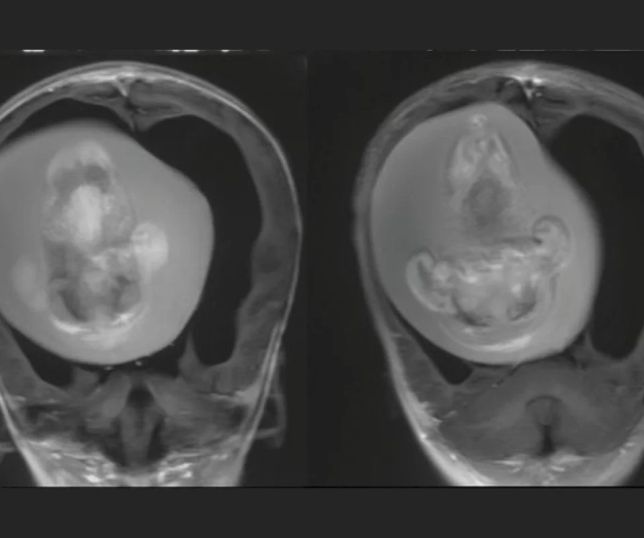

Médicos retiram feto da cabeça de bebê